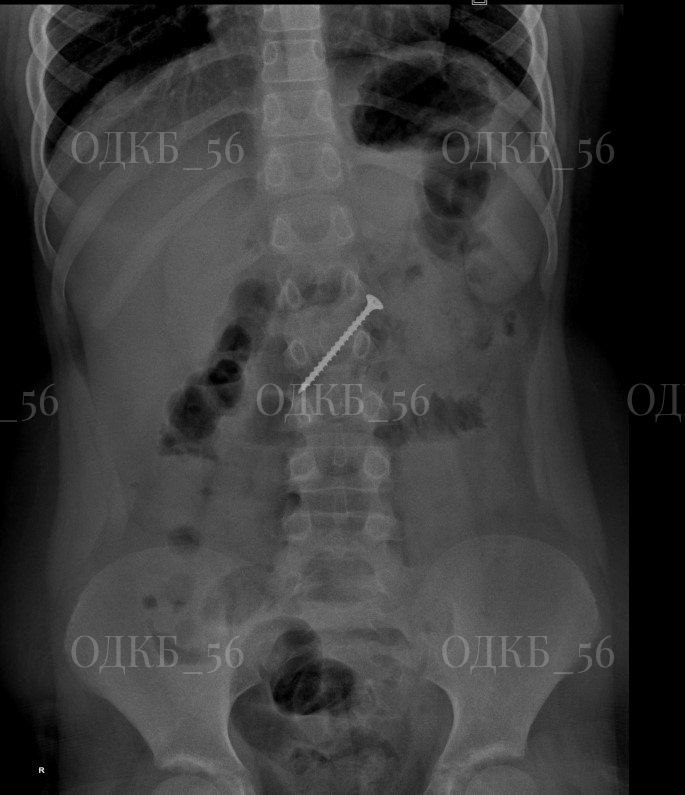

Обследование подтвердило опасения родителей: рентгенография показала наличие инородного тела в области желудка. В экстренном порядке команда специалистов провела эндоскопию верхних отделов ЖКТ под общим обезболиванием.

Во время операции выяснилось, что саморез длиной около 5 см мигрировал в двенадцатиперстную кишку, что создавало прямую угрозу жизни ребенка. Был риск развития кишечной непроходимости или перфорации стенки кишки. Врачам удалось извлечь опасный предмет. В настоящее время маленький пациент был выписан домой в удовлетворительном состоянии.